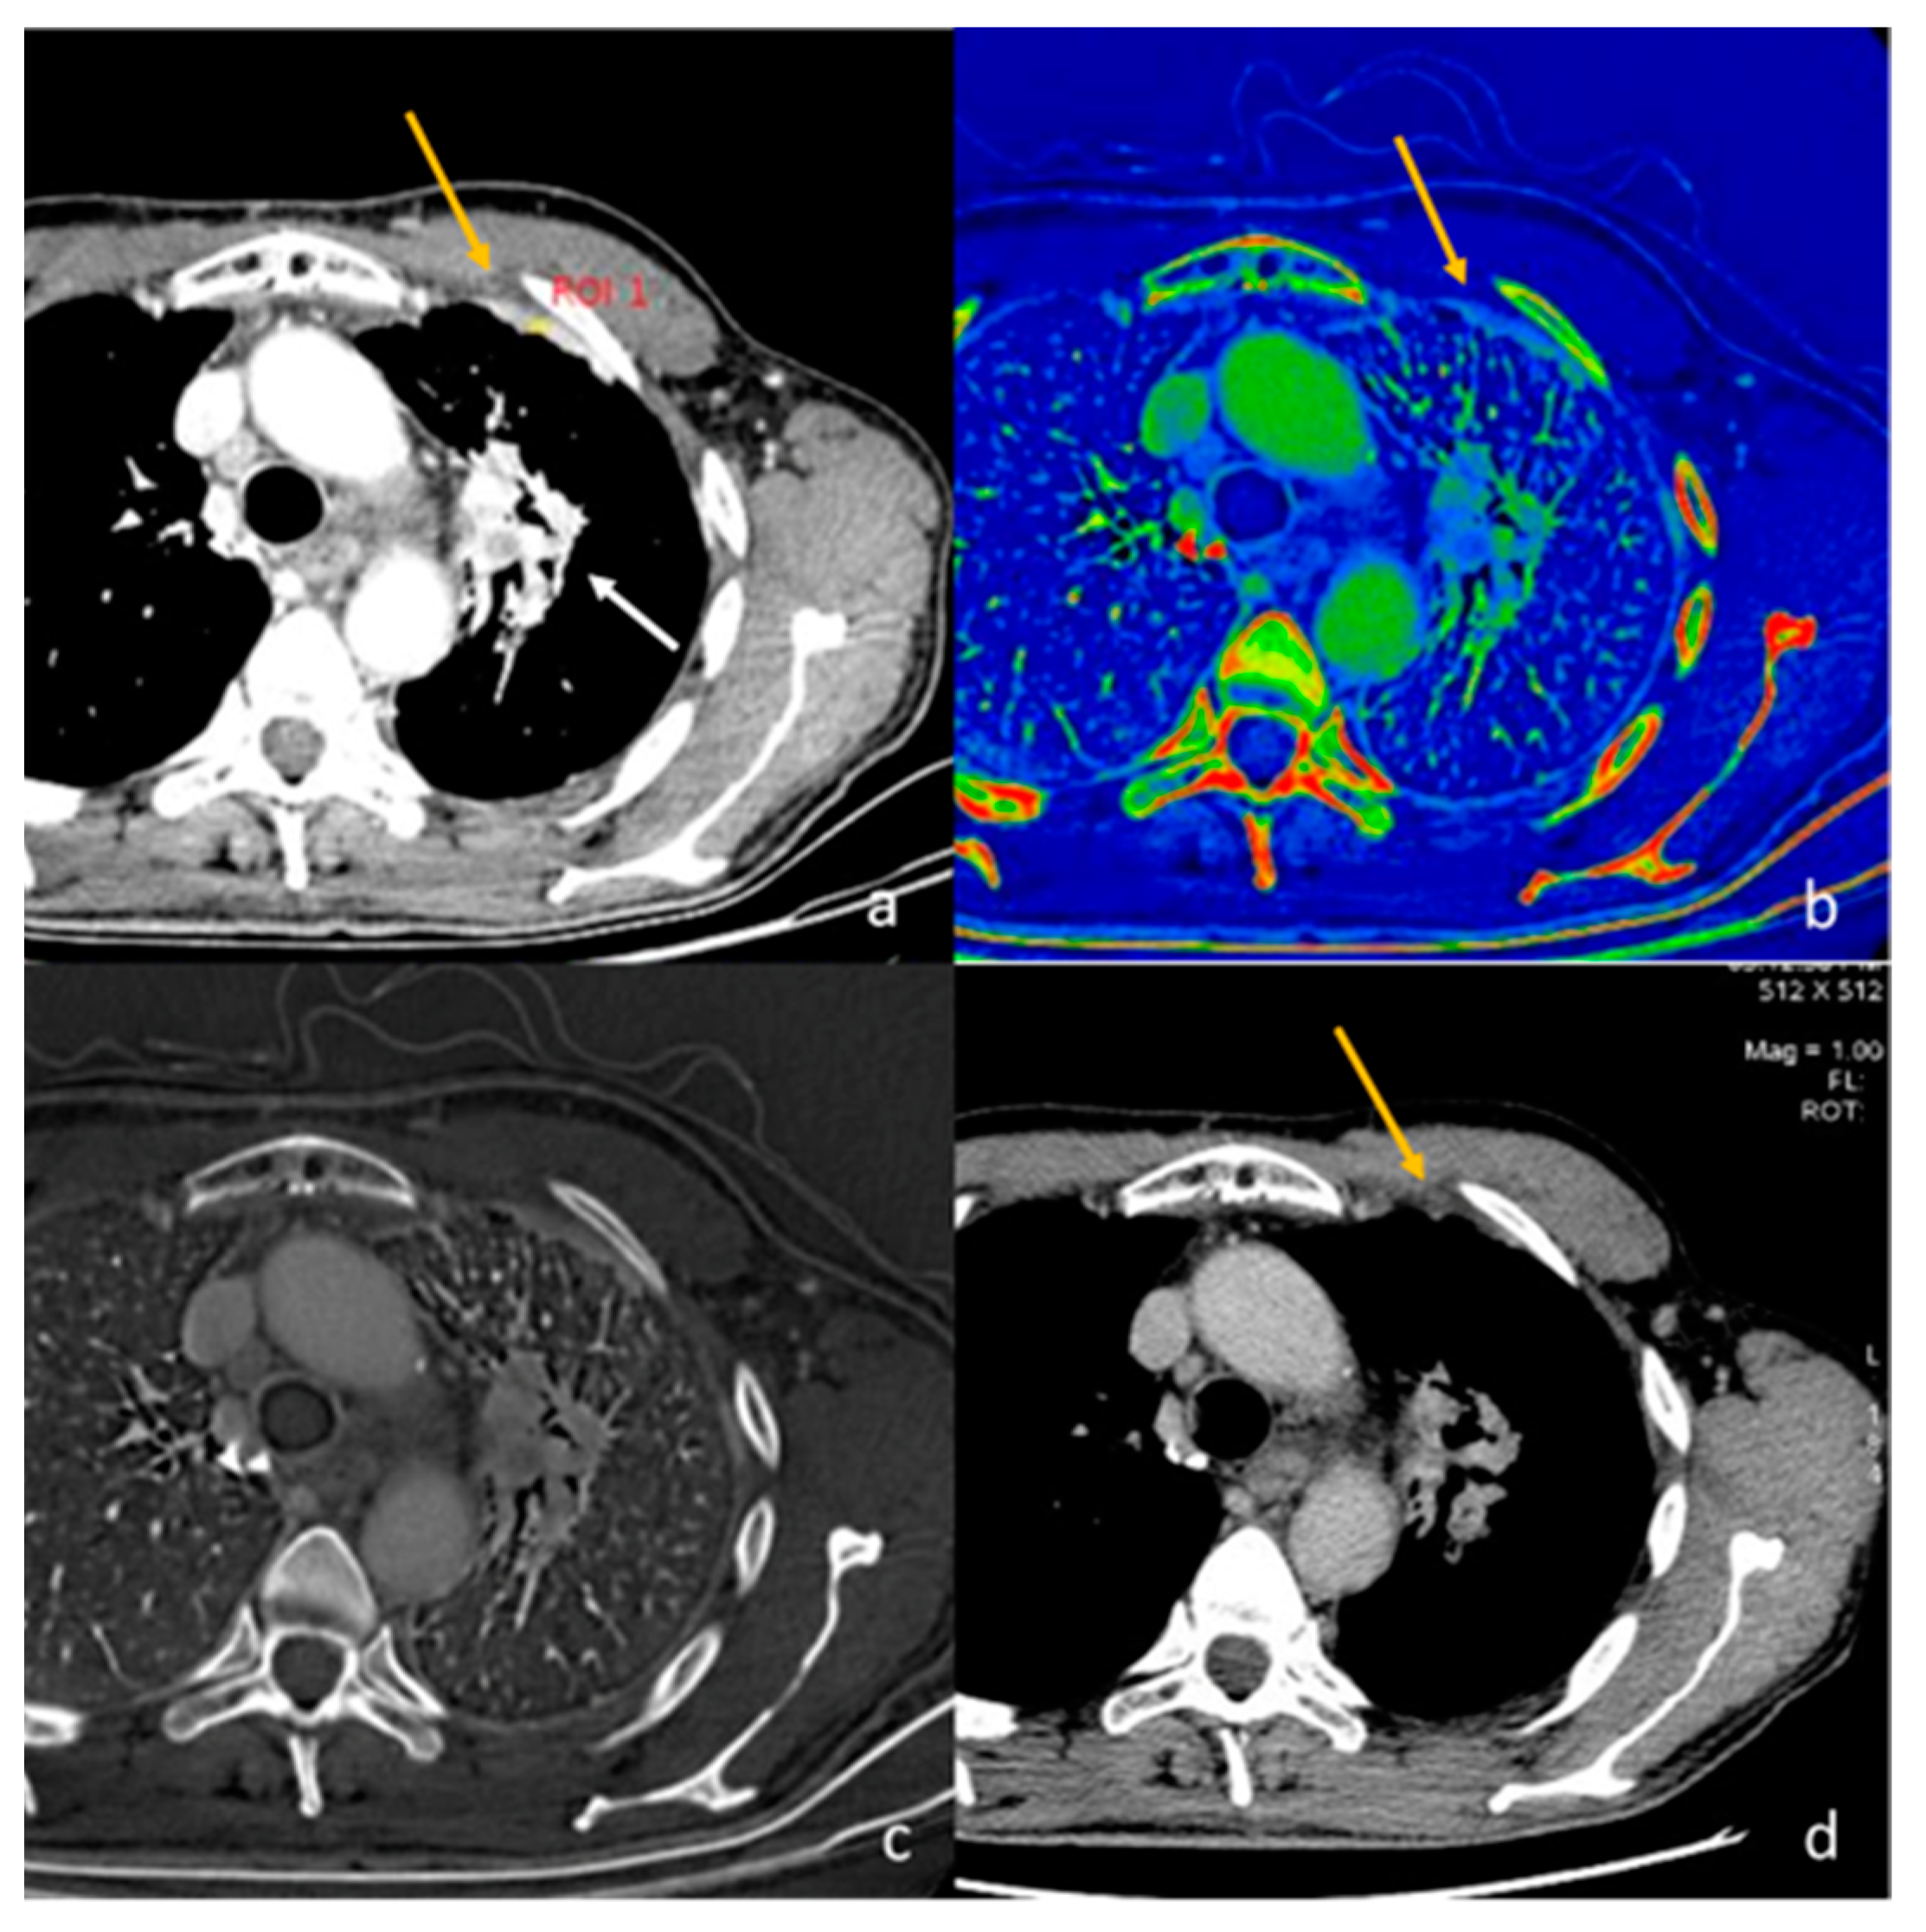

- Volterrani, L.; Gentili, F.; Fausto, A.; Pelini, V.; Megha, T.; Sardanelli, F.; Mazzei, M.A. Dual-Energy CT for Locoregional Staging of Breast Cancer: Preliminary Results. Am. J. Roentgenol. 2020, 214, 707–714. [Google Scholar] [CrossRef] [PubMed]

| Wang et al. [56] Retrospective study | China | To objectively and subjectively assess and compare the characteristics of mono-energetic images and poly-energetic images acquired by DECT of patients with breast cancer | 42 | SOMATOM Drive, Siemens Healthineers No C.I. | Reconstructions at low keV in the venous phase acquired by DECT improved the objective and subjective assessment of lesion conspicuity in patients with malignant breast lesions. |

| Volterrani et al. [57] Retrospective study | Italy | To demonstrate the feasibility of DECT for locoregional staging of breast cancer and differentiation of tumor histotypes | 31 | Discovery CT 750 HD, GE Healthcare No C.I. | DECT is feasible and seems to be a reliable tool for locoregional staging of breast cancer. |

| Moon et al. [58] Retrospective study | South Korea | To evaluate the predictive value of VMI by assessing tumor conspicuity on dual-layer spectral detector CT and correlate tumor conspicuity on VMI with prognostic biomarkers in patients with breast cancer | 64 | IQon Spectral CT, Philips Health System No C.I. | VMI40DEL may be useful in the diagnosis of breast cancers due to higher tumor conspicuity and better enhancement than VMI40ART. VMI40ART may be beneficial for the prediction of poor breast cancer prognoses. |